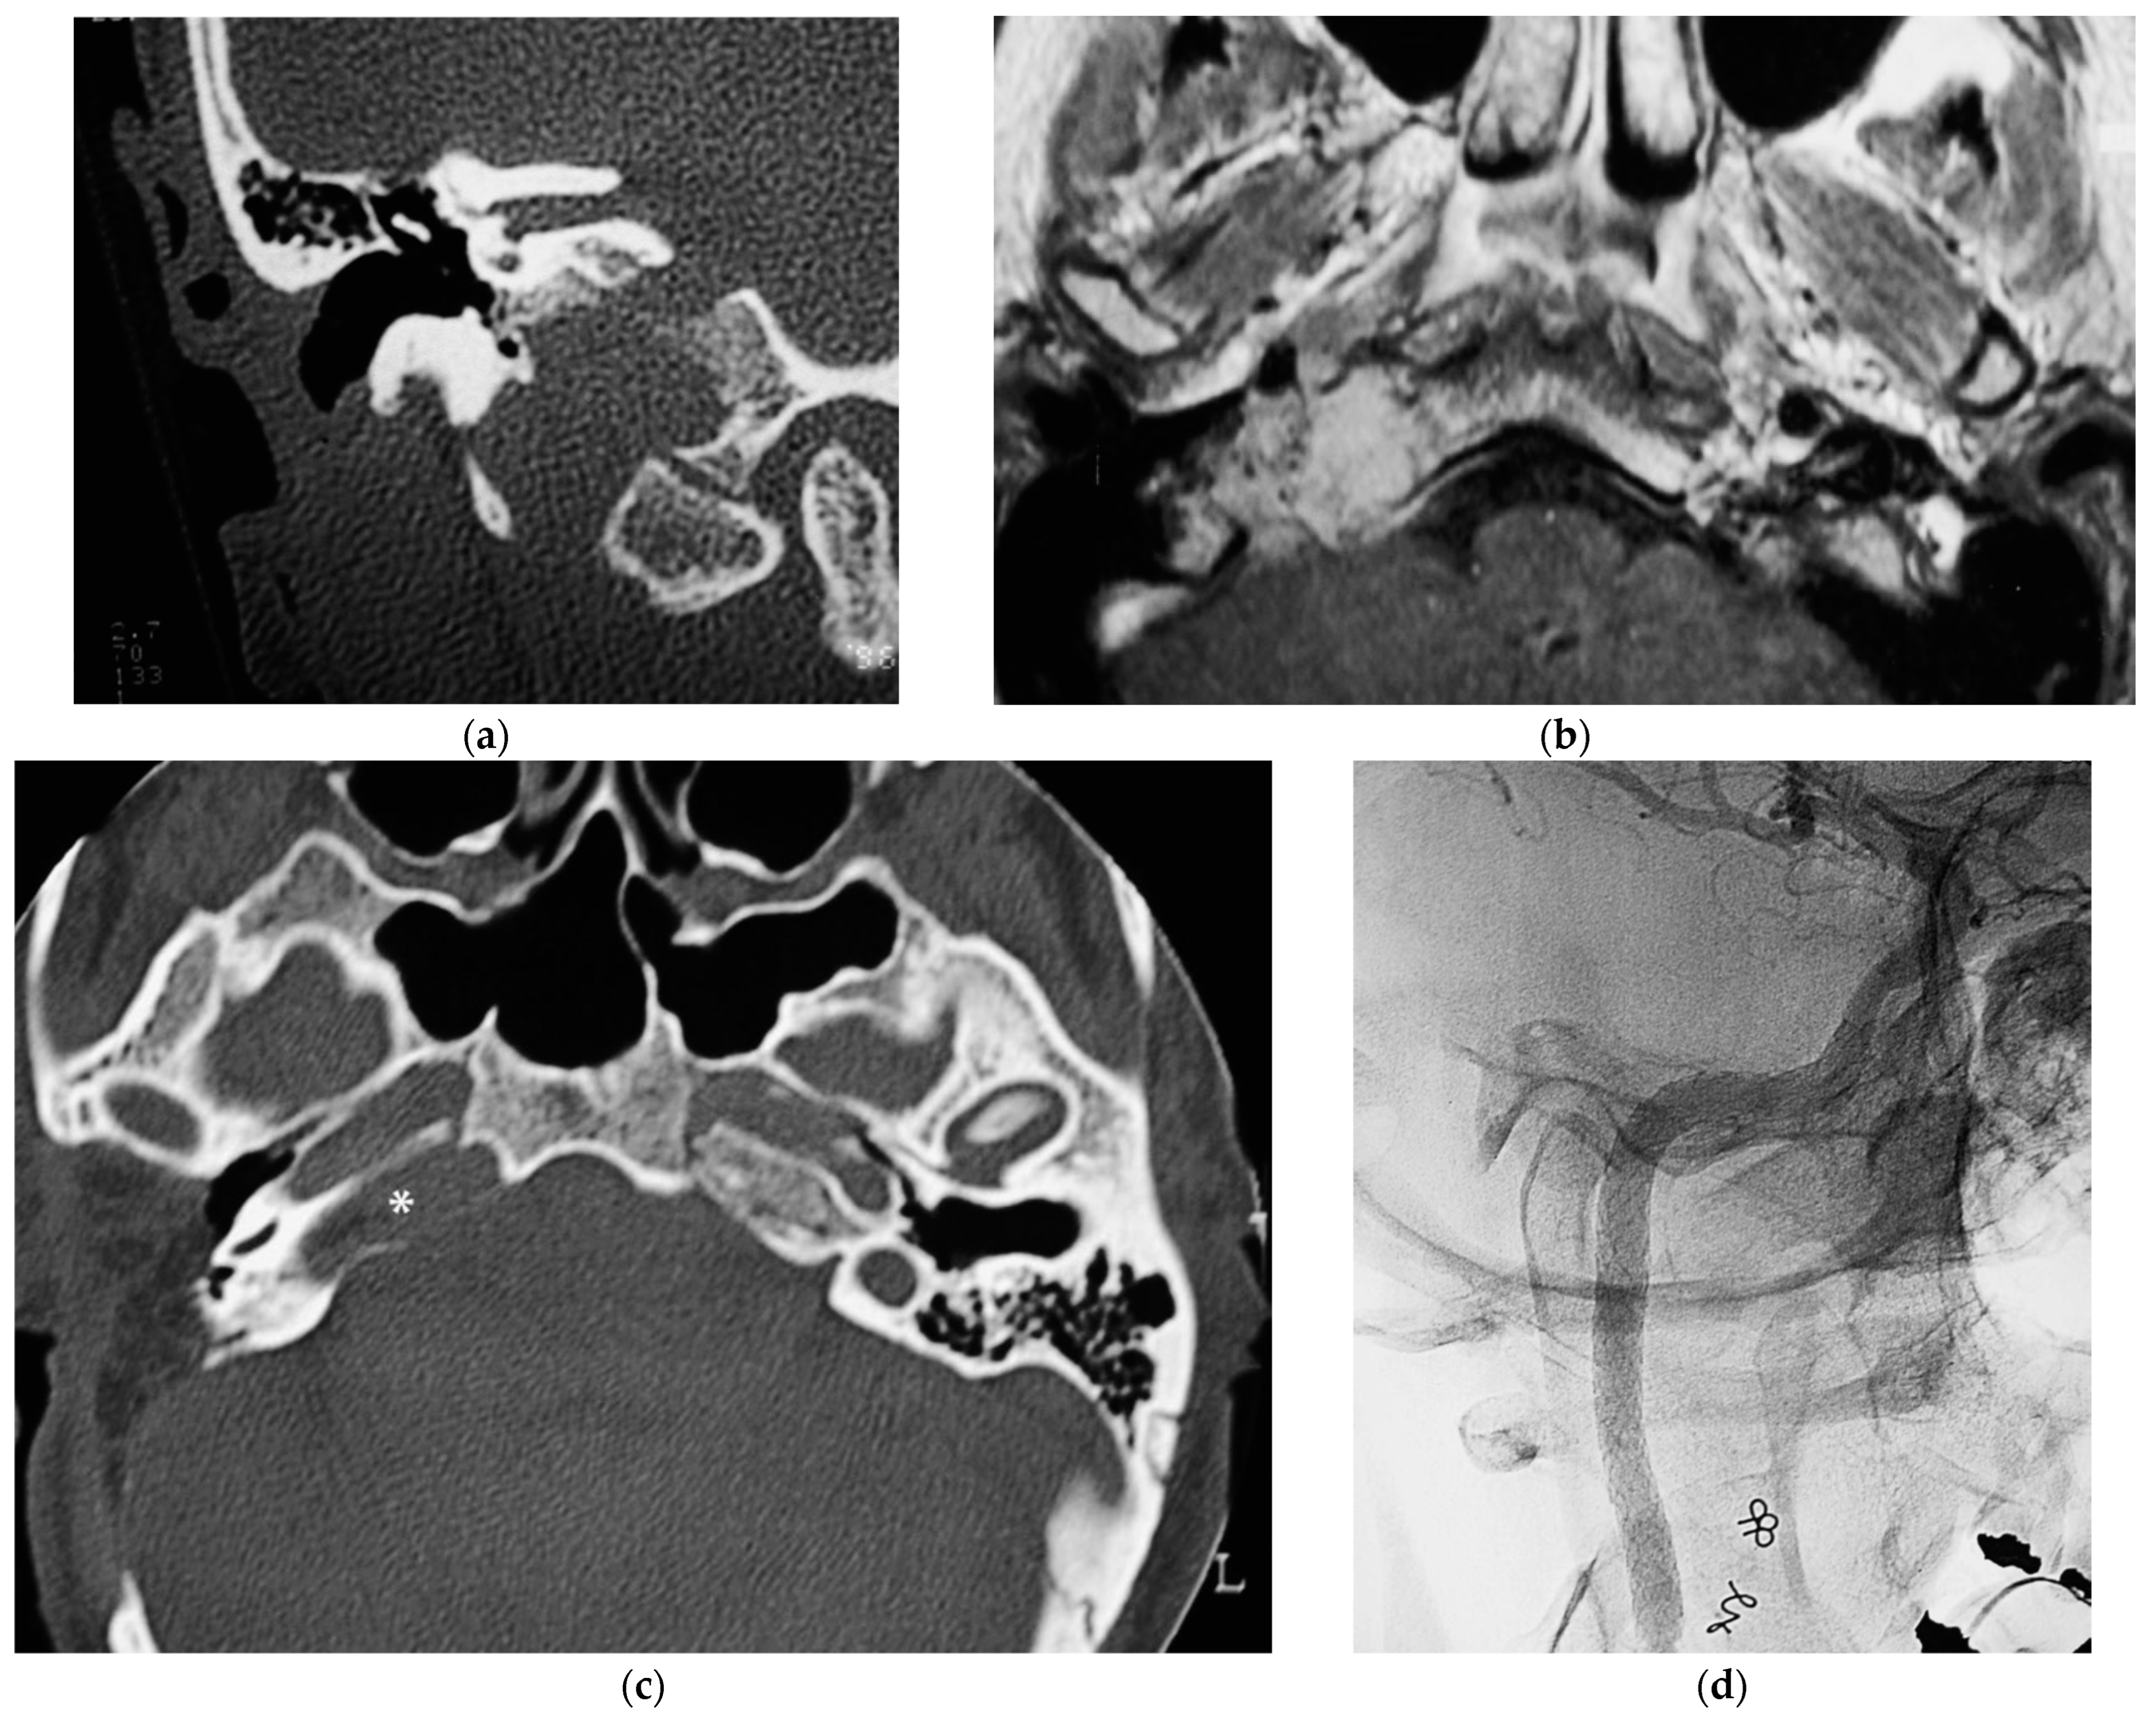

5.1. Case 1: (C4Di2)